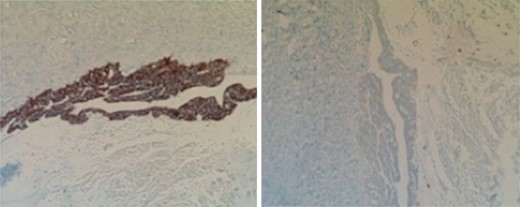

Subsequent surgical pathology results confirmed two separate malignant processes causing the carcinomatosis: Immunohistochemical examination was performed on the surgical specimens. The appendiceal tumor stained negative for CK-7 and positive for CK-20 (Fig. 1), whereas the ovarian sample stained positive for CK-7 and negative for CK-20 (Fig. 2), consistent with malignant processes of independent origins.

Perforated mucinous adenocarcinoma of the appendix arising from villous adenoma, at least 8.5 cm invading into subserosa and into adjacent ileal and cecal serosa with widespread involvement of omentum (carcinomatosis).

Left perforated ovarian mucinous adenocarcinoma with widespread involvement of fallopian tube and subserosa of sigmoid colon (carcinomatosis).